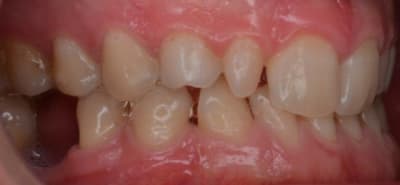

Voici un jeune homme de 20 ans et demi très complexé par l'esthétique de ses dents : fronts supérieur et inférieur en rétrusion, les centrales qui descendent trop, les latérales riziformes, les canines de lait toutes blanches et toutes petites, les canines définitives bien logées dans l'os au dessus. En plus d'être complexé par son sourire, il voudrait entrer dans une voie professionnelle où l'apparence a beaucoup d'importance.

Que proposeriez-vous à ce patient pour améliorer sa situation esthétique ? Facettes 12 à 22 pour réharmoniser tout ça et facette compo sur les canines de lait (j'imagine que proposer des facettes céramiques sur des dents de lait n'est pas une bonne idée !) ? Facettes seulement sur les latérales et compo canines ? Extraction canines de lait et implants ?.... J'ai bien peur de vite tomber dans le surtraitement...